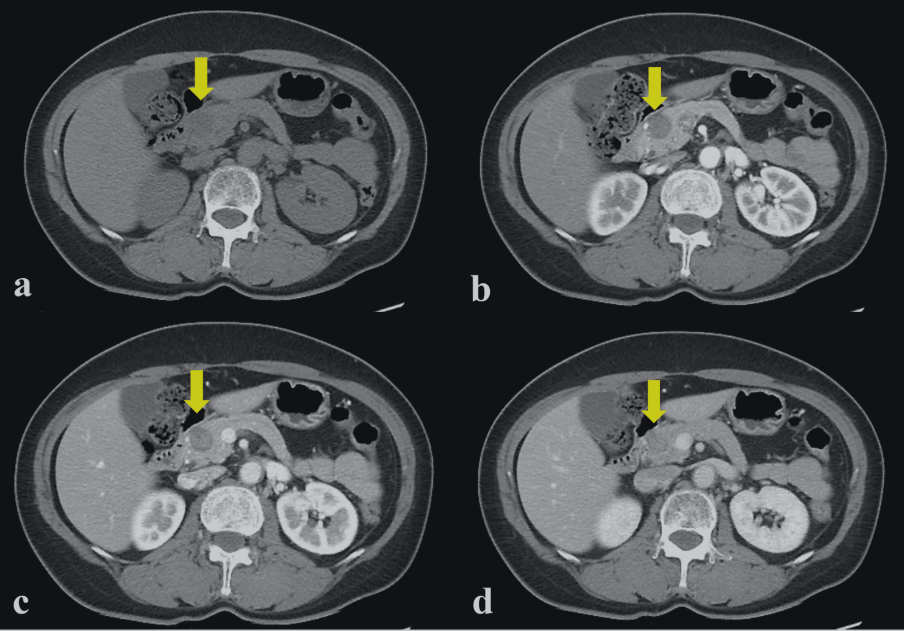

图 2.2 计算机断层扫描(CT)显示在胰腺头部 (a) 有一个低密度肿块,大小为 20×20 mm 动脉 (b) 期、门静脉 (c) 期和静脉 (d) 期的动态 CT 显示边界清晰的实性肿块,呈轻微、逐渐、不均匀的强化(黄色箭头)。